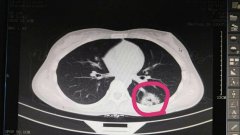

日前,我院急診科接到120通知,接回一車禍病人,入院時表述胸腹部疼痛,并呈現(xiàn)出血壓下降……